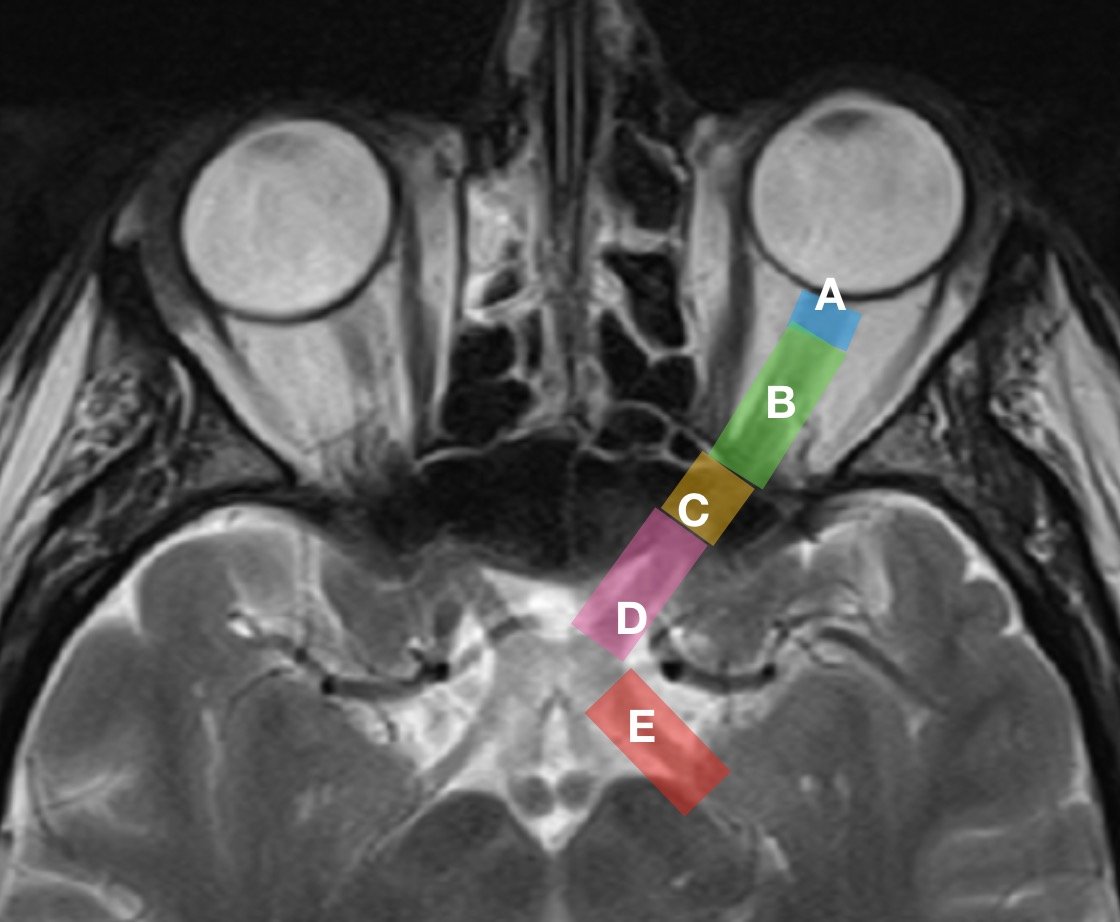

From www.aao.org

Optic nerve sheath American Academy of Ophthalmology Optic Nerve In Your Ear Your brain takes those signals,. Your optic nerve is the connection that lets your eyes send signals to your brain describing what they detect. The visual reflexes, optic radiation,. This article will review the embryology, anatomy, histology, and blood supply of the optic nerve, as well as briefly discuss the optic tracts. It is developed from the optic. Optic neuritis. Optic Nerve In Your Ear.